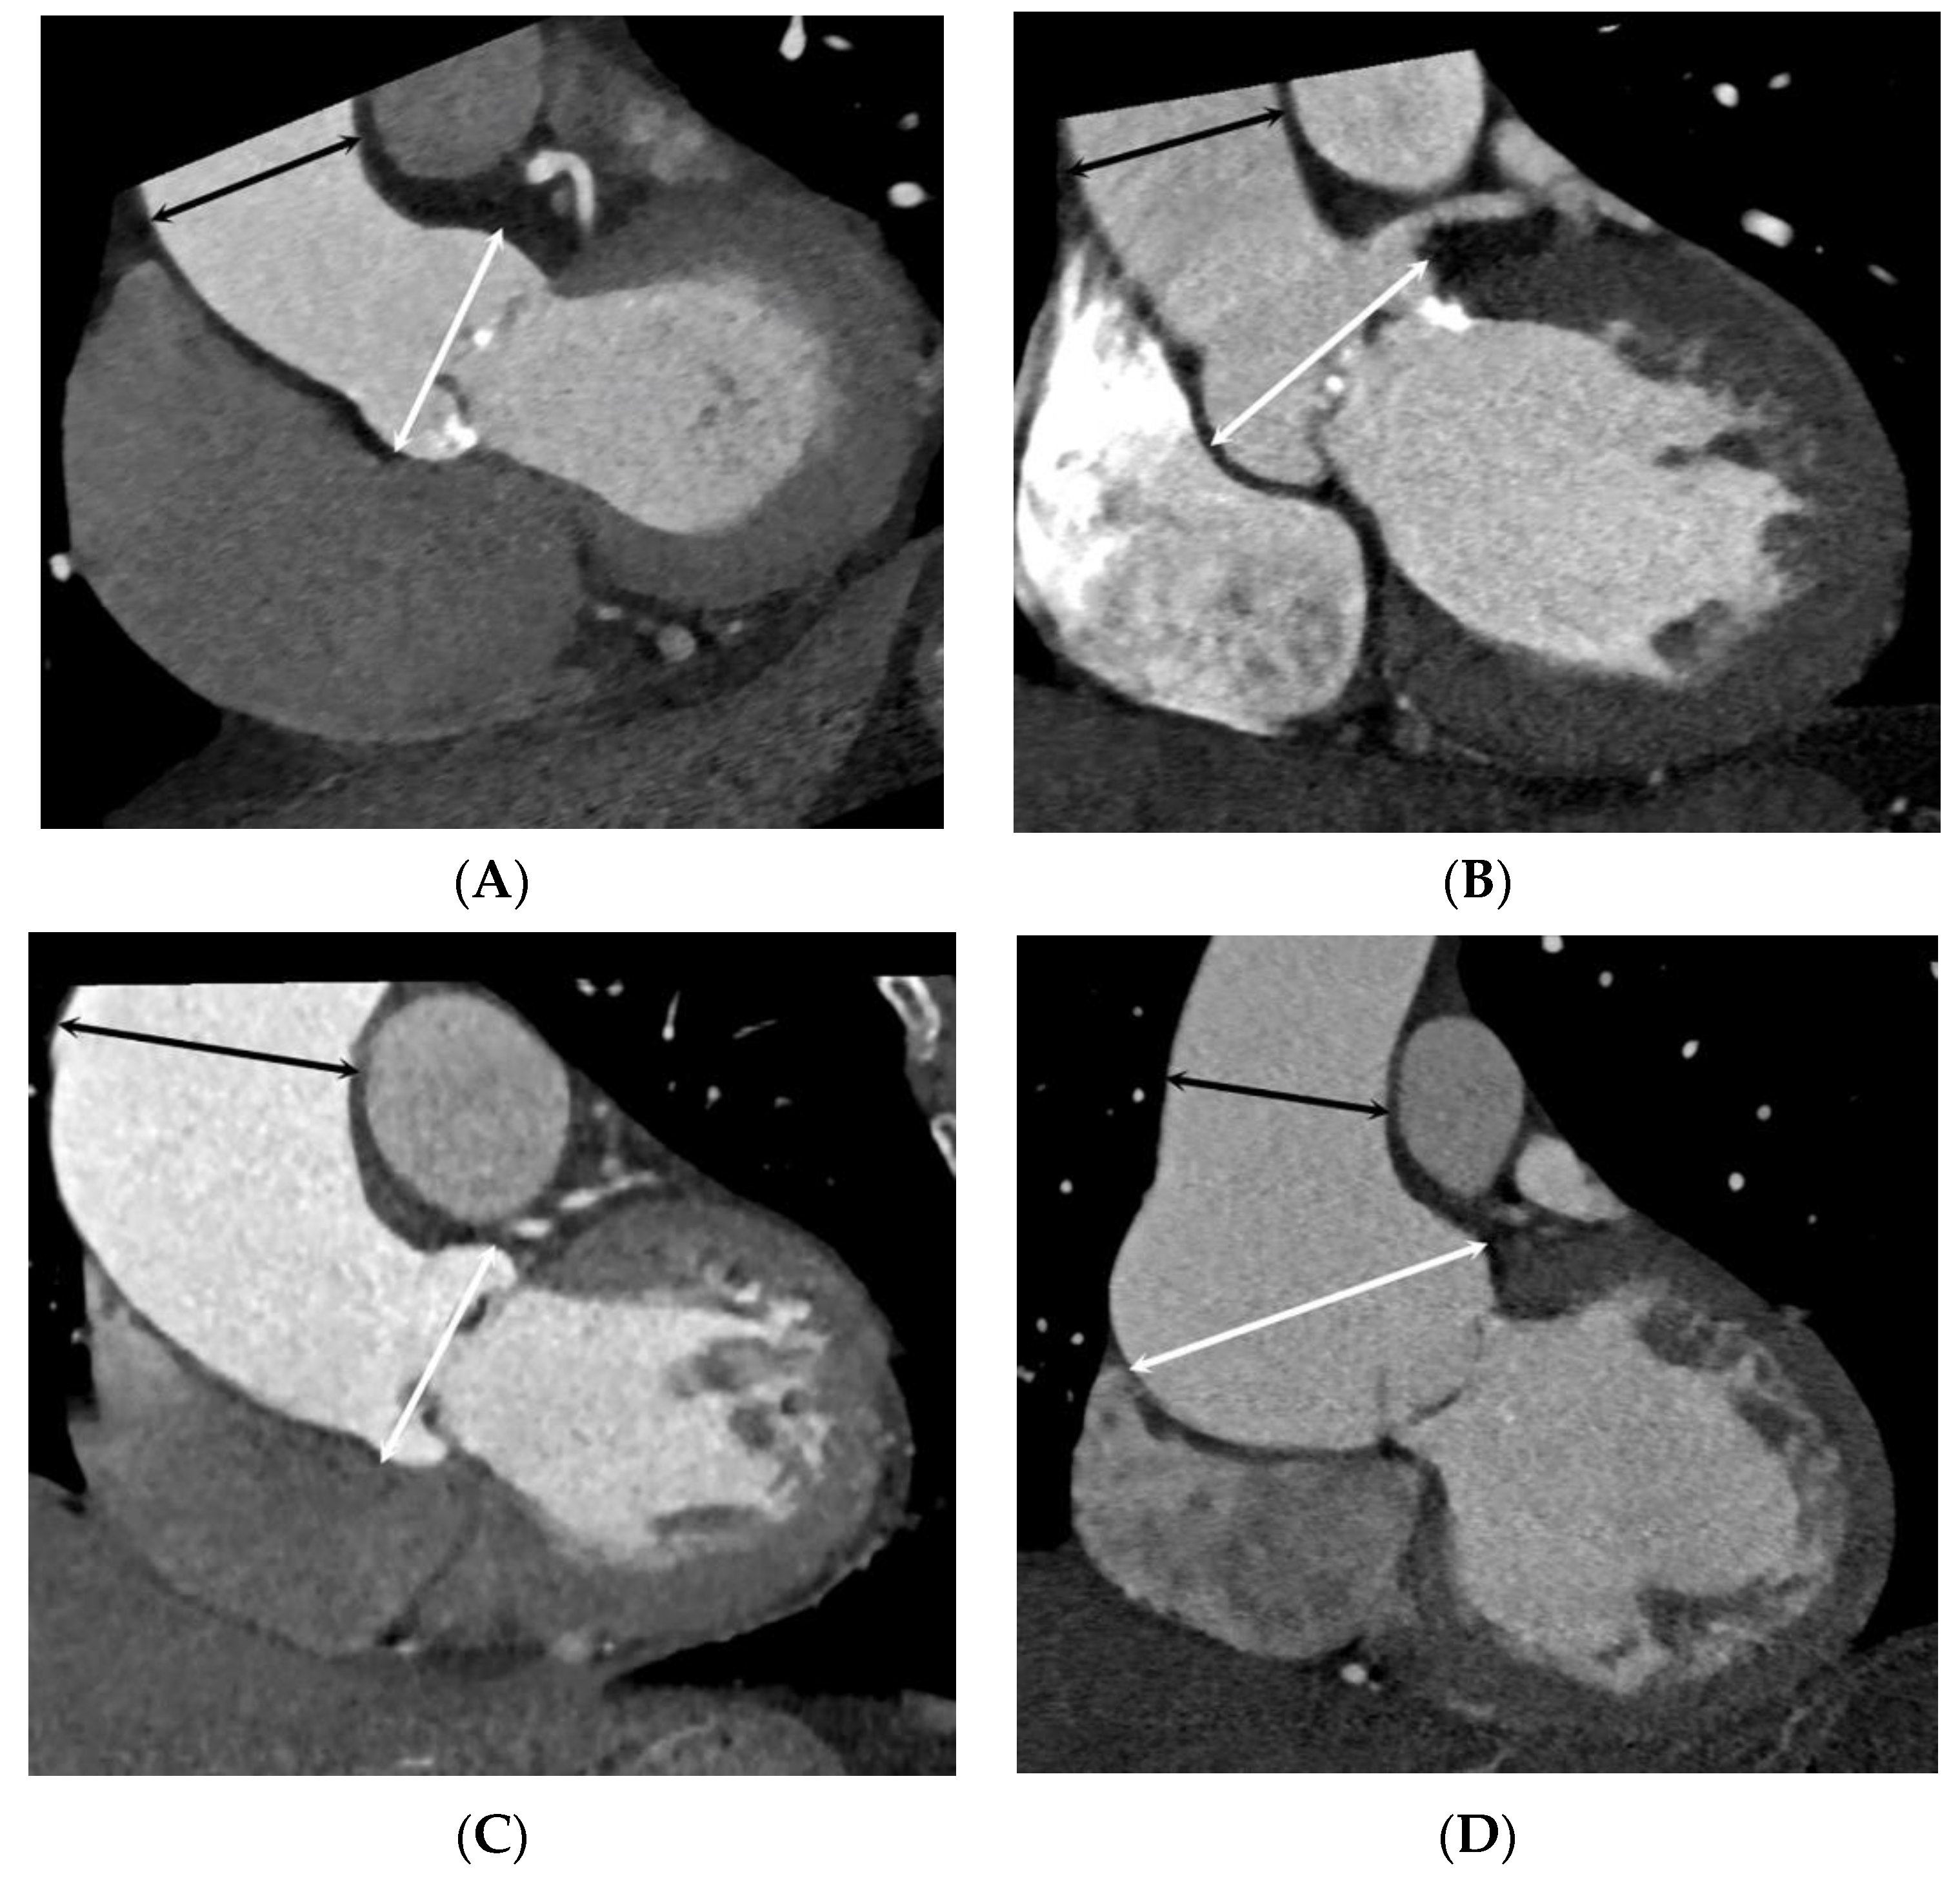

2.2. CT Imaging Protocols

2.3. CT Image Reconstruction and Analysis